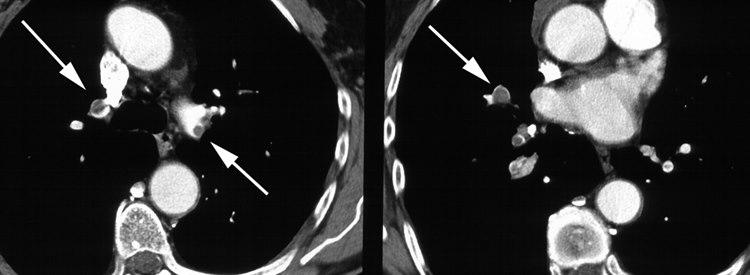

Røntgenbilde av lunger med blodproppDiagnosen kan noen ganger være vanskelig å stille i tidlig fase eller ved små blodpropper. Vanlige symptomer på blodpropp i lungene er:

Diagnosen kan være vanskelig å stille. Mistanke om lungeemboli på grunnlag av sykehistorien fører alltid til akutt innleggelse på sykehus. Der vil det bli tatt blodprøver, blant annet for å påvise eller utelukke andre sykdommer som kunne medført disse plagene. Lungene vil bli grundig undersøkt, og en spesiell CT-undersøkelse av blodårene i lungene kan gi sikkert svar.